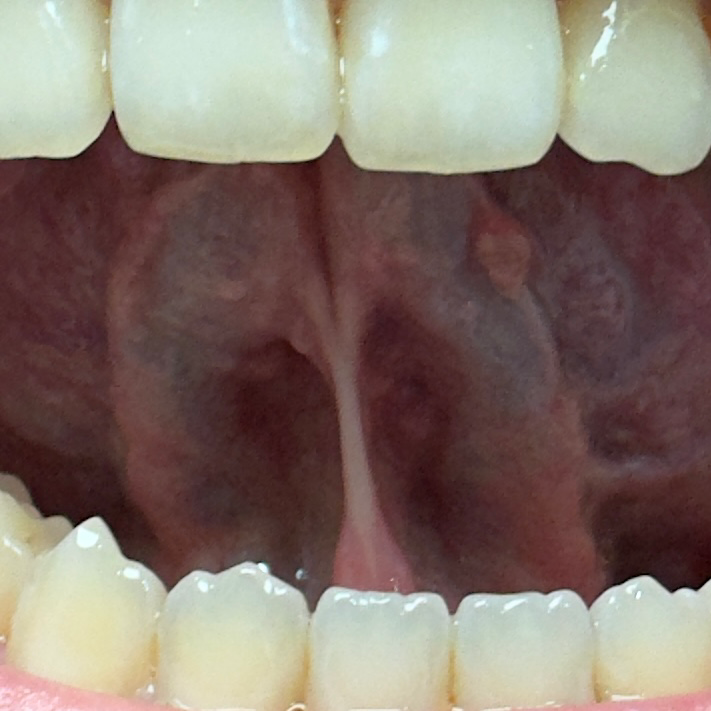

혀 아래 부분에 돌기?뾰루지?같은게 있어요

혀 아래 부분에 돌기나 뾰루지 같은게 많이 있어요.

• 1번 째 사진

특별히 병적인 상태로 보이지는 않습니다. 점차 모양이나 크기의 변화가 저명하다면 이비인후과나 구강전문의를 방문해보시기 바랍니다.